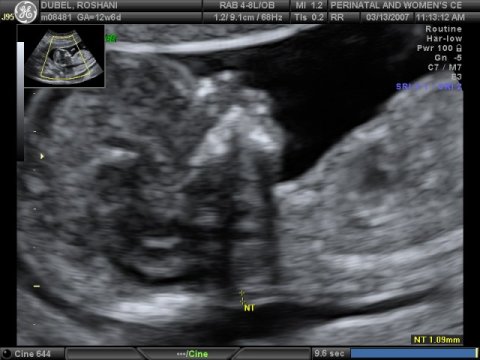

March 14, 2007

The

due date for Baby Miracle keeps changing. Original due date was

September 06, 2007, but an early ultrasound suggested September 19,

2007. Latest ultrasound, done on March 13, 2007, suggest that the

baby is expected to arrive September 09, 2007. It's still too

early to tell the sex of the baby but we should know by late

April/early May.

Baby waves "hello"